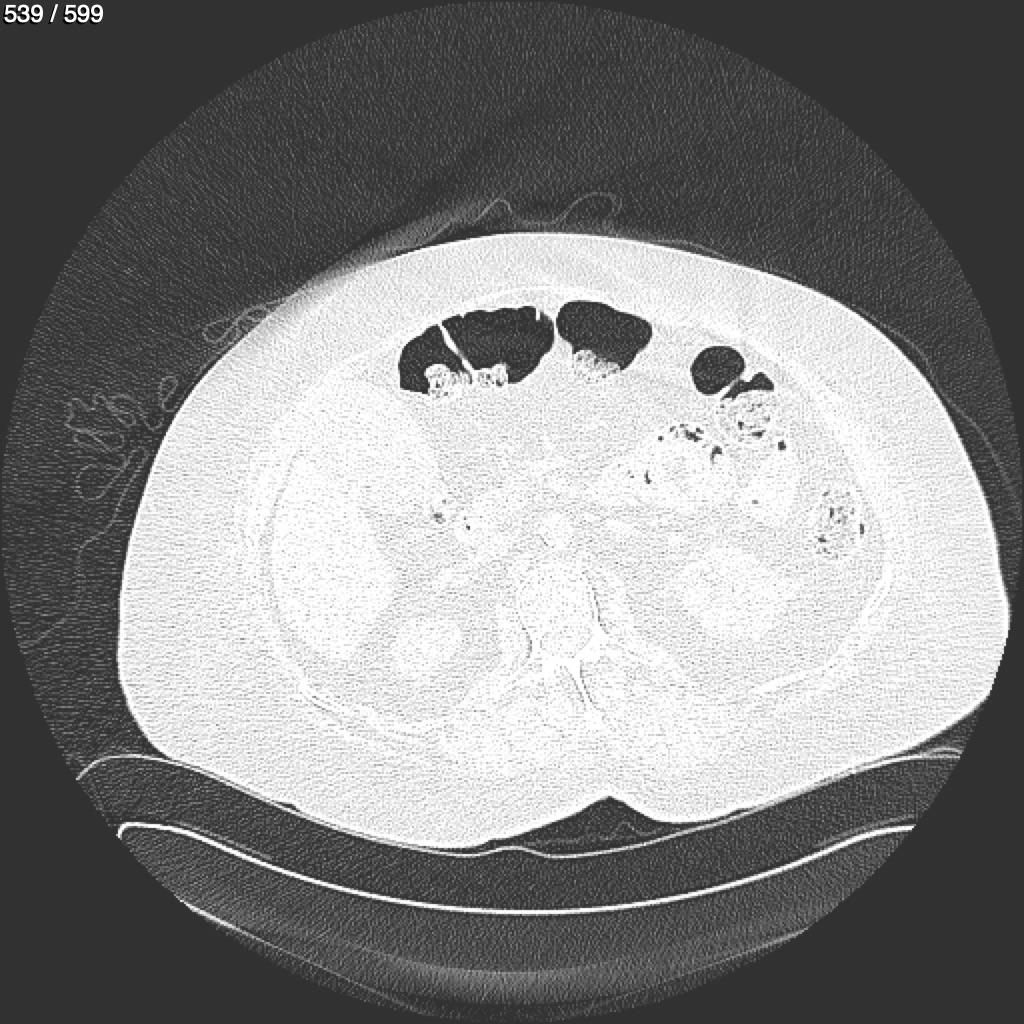

Home G​l​o​r​i​a​ ​G​l​a​d​y​s​ ​B​e​a​s​l​e​y​ ​-​ ​T​ó​r​a​x​ ​T​o​r​a​x​_​S​i​m​p​l​e​ ​(​A​d​u​l​t​o​)